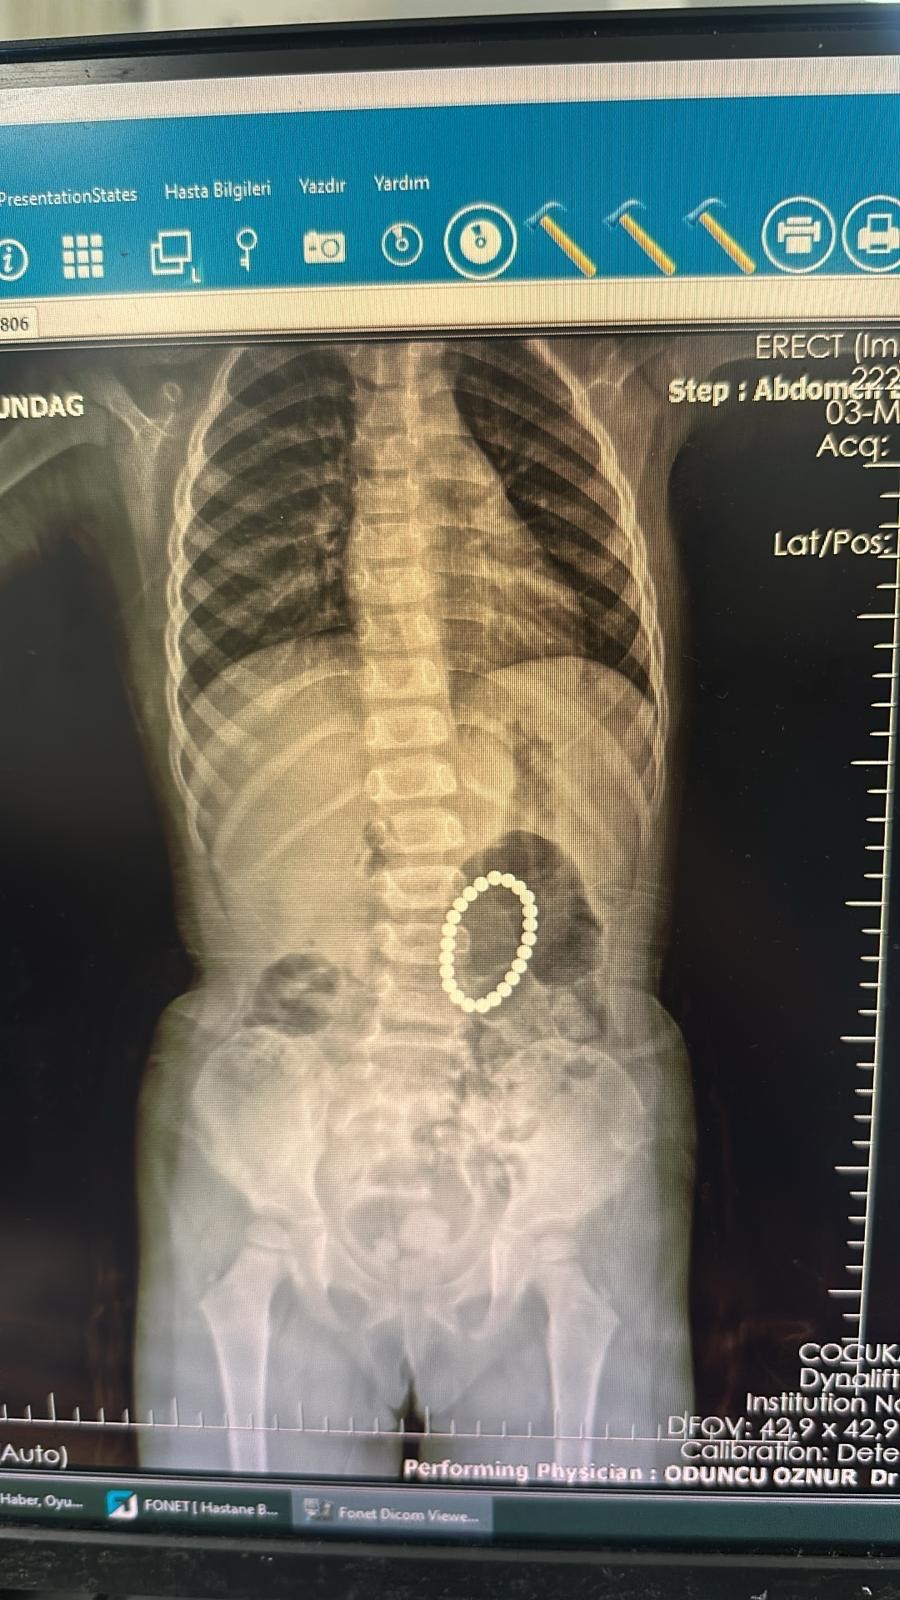

Yapılan endoskopide küçük kızın bağırsaklarında ve midesinde bileklik şeklinde yabancı cisimlerin olduğu belirlendi. Ameliyata alınan Rumeysa Altundağ'ın bağırsakları ve midesinden 24 adet renkli oyuncak mıknatıs çıkartıldı.

Mıknatısların bağırsaklarda kısmen delinmelere neden olduğunu belirten Dr. Özkaya, "Hastamız 4 yaşında kız hasta. Yoğun karın ağrısı nedeniyle Şırnak'ta devlet hastanemize başvurmuş, yapılan tetkiklerinde yabancı cisim yuttuğu tespit edilmiş. Bunun üzerine endoskopi yapılmak üzere hastanemize Gastroentoloji bölümüne sevk edildi. Endoskopi sırasında tespit edilen yabancı cisimlerin renkli mıknatıslar olduğu, yarısının da midede gözükmediği görüldü. Hastamız 24 tane renkli küçük mıknatıs yutmuştu. Endoskopi işleminden sonra hastamıza operasyon planladık. Yaptığımız ameliyatta da farklı zamanda yutulan mıknatısların yarısının midede yarısının bağırsaklarda olduğu ve bunların birbirine yapışarak bağırsak kısımlarında delinmelere neden olduğu görüldü. Bu kısımları onardık. Hastamız ameliyattan sonra beslenmesine de başladı, herhangi bir sıkıntısı yok, taburcu etmeyi planlıyoruz" dedi.